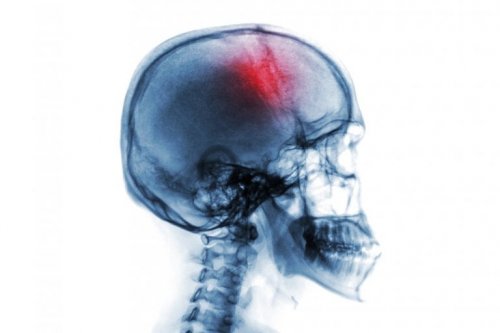

Apoplexie (Schlaganfall): Risikofaktoren und Symptome

Eine Apoplexie, oder auch Apoplex, Schlaganfall oder Hirnschlag, ist eine plötzliche Durchblutungsstörung im Gehirn. Es handelt sich um einen medizinischen Notfall. Wenn die Durchblutung des Gehirns gestört ist, kommt es nämlich zum Absterben von Gehirngewebe. Dies wiederum führt zu einem neurologischen Defizit, was eine Diskapazität oder auch den Tod zur Folge haben kann.

- Es könnte jedoch auch eine Gehirnblutung vorliegen, dann spricht man von einem hämorrhagischen Schlaganfall.